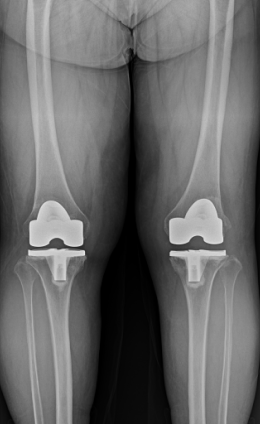

수술적 치료 : 인공관절 치환술

말기

인공관절 치환술

노화에 따른 퇴행성 관절염,외상 후 발생되는 외상성 관절염 등으로 손상이 심한 관절, 관절의 심한 변형과 극심한 통증을 해결하는 데 효과적으로 개인에게 맞게 인공 대체물을 삽입하는 수술 방법입니다.

무릎 관절 연골이 일부만 닮아 있을 경우, 선택적으로 인공관절 부분치환술을 시행 할 수 있습니다.적응증 (누가 하는가)

수술 전후 사례

-

수술 전

수술 후